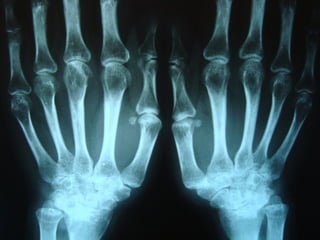

 Articulações das mãos (punhos,IFP e MCF)Articulações das mãos (punhos,IFP e MCF)

MTF,cotovelos,tornozelos,joelhos,ombros eMTF,cotovelos,tornozelos,joelhos,ombros e

articulações dos quadris são mais frequentes.articulações dos quadris são mais frequentes.

 Sinovite simétricaSinovite simétrica

 Rigidez matinal de pelo menos 1 horaRigidez matinal de pelo menos 1 hora

ARTICULAÇÕES ACOMETIDAS

NA ARTRITE REUMATÓIDE

Envolvimento moderado inicial doEnvolvimento moderado inicial do

pulso,MCF e articulações IFPpulso,MCF e articulações IFP

Achados radiográficosAchados radiográficos

 Osteopenia peri-articularOsteopenia peri-articular

 Diminuição do espaço articularDiminuição do espaço articular

 Presença de cisto e erosõesPresença de cisto e erosões

 Edema de partes molesEdema de partes moles

 Presença de deformidadesPresença de deformidades

1- osteopenia 2-erosões 3-sub-luxação